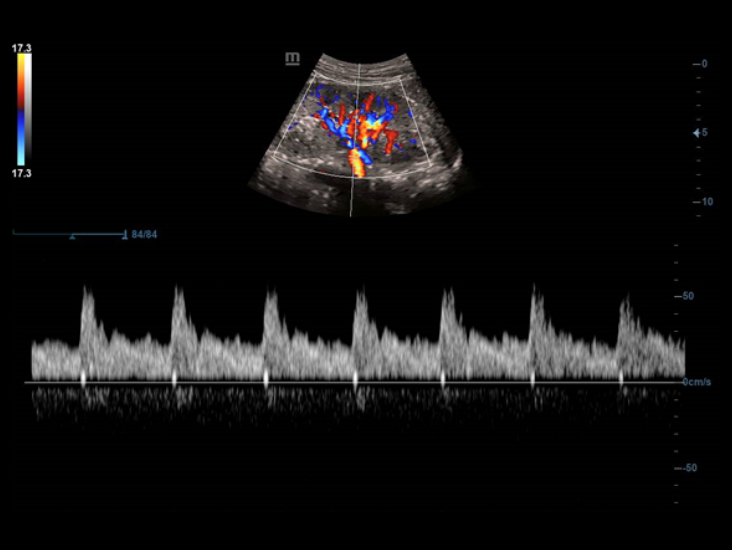

–†–Β―à–Β–Ϋ–Η–Β –¥–Μ―è ―É―Ä–Ψ–Μ–Ψ–≥–Η–Η

–Γ–Ω–Β―Ü–Η–Α–Μ―¨–Ϋ–Ψ ―Ä–Α–Ζ―Ä–Α–±–Ψ―²–Α–Ϋ–Ϋ―΄–Β –±–Η–Ω–Μ–Α–Ϋ–Ψ–≤―΄–Β –¥–Α―²―΅–Η–Κ–Η, –≤ ―²–Ψ–Φ ―΅–Η―¹–Μ–Β –Μ–Η–Ϋ–Β–Ι–Ϋ―΄–Β/–Κ–Ψ–Ϋ–≤–Β–Κ―¹–Ϋ―΄–Β –Η –¥–≤–Ψ–Ι–Ϋ―΄–Β –Φ–Η–Κ―Ä–Ψ–Κ–Ψ–Ϋ–≤–Β–Κ―¹–Ϋ―΄–Β, –Ψ–±–Β―¹–Ω–Β―΅–Η–≤–Α―é―² ―É–Ϋ–Η–≤–Β―Ä―¹–Α–Μ―¨–Ϋ–Ψ–Β ―É―Ä–Ψ–Μ–Ψ–≥–Η―΅–Β―¹–Κ–Ψ–Β ―Ä–Β―à–Β–Ϋ–Η–Β –¥–Μ―è ―Ä–Α―¹―à–Η―Ä–Β–Ϋ–Η―è –£–Α―à–Η―Ö –≤–Ψ–Ζ–Φ–Ψ–Ε–Ϋ–Ψ―¹―²–Β–Ι.